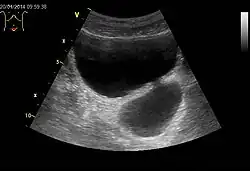

- Divertikel des Darmes (Darmdivertikel)[1] sind vorwiegend im Dickdarm (insbesondere im Sigmoid) anzutreffen. Sie entstehen durch einen Prolaps der Schleimhaut durch die Muskellücken der Darmwand, sind also meistens Pseudodivertikel. Diese Muskellücken sind eigentlich Durchtrittsstellen der Darmwandgefäße und stellen somit einen Prädilektionsort für die Divertikelbildung dar. In einigen Fällen kann das Divertikel zunächst intramural (innerhalb der Darmwand) verlaufen, im späteren Verlauf nimmt die Ausstülpung der Schleimhaut an Größe zu und die Divertikel können symptomatisch werden. Häufig ist dies der Fall im höheren Lebensalter (> 60 Jahre). Als Ursache der Schleimhautausstülpung wird ein erhöhter Darminnendruck (= intraluminaler Druck) vermutet, der wiederum durch einen zu geringen Ballaststoffgehalt der Nahrung entstehen soll. Eine aktuelle Studie konnte jedoch keinen Schutzeffekt durch einen hohen Ballaststoffgehalt nachweisen.[2] Rektumdivertikel sind beim Menschen äußerst selten, kommen aber beim Hund, insbesondere im Zusammenhang mit einer Perinealhernie, häufiger vor.[3]

Bei einer Divertikulose (Divertikelkrankheit) liegen viele Divertikel vor. Diese verursachen grundsätzlich keine Beschwerden. Entwickeln sich bei einer Divertikulose Beschwerden, ist von einer symptomatischen unkomplizierten Divertikelkrankheit (SUD) die Rede. Die auftretenden unterschwelligen chronischen Entzündungen sind dabei lokal begrenzt.[4] Erst bei einer Divertikulitis kommt es zur Entzündung eines oder mehrerer dieser Divertikel.